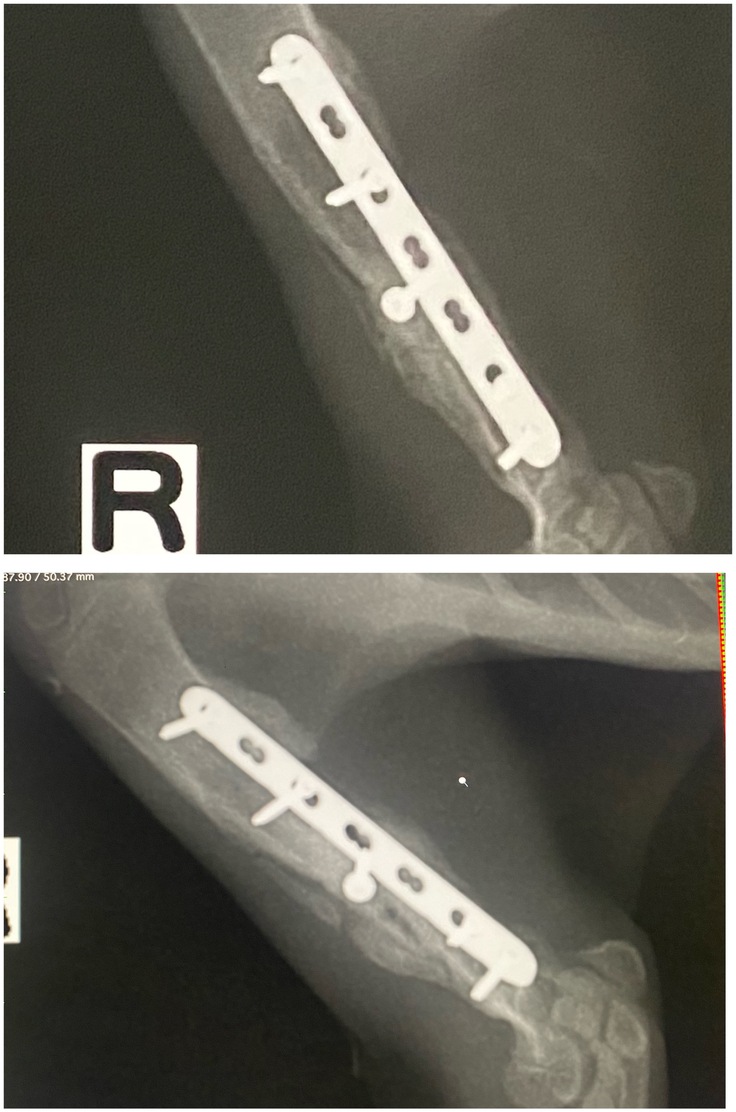

左後足

←今日 前回→

前回とくらべてゴツゴツした感じがなくなりました。古い骨が吸収され新しい骨が形成されていきます。膝より下も骨が伸び、タビちゃんもしっかり成長しています。